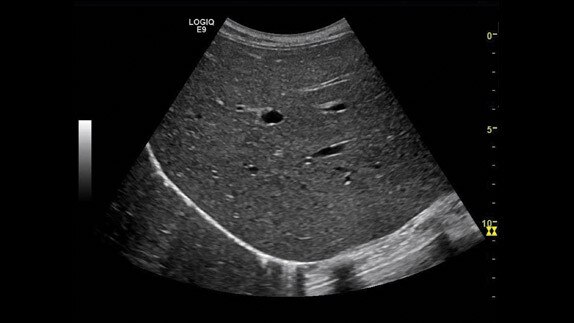

Karaciğer, 9L probu